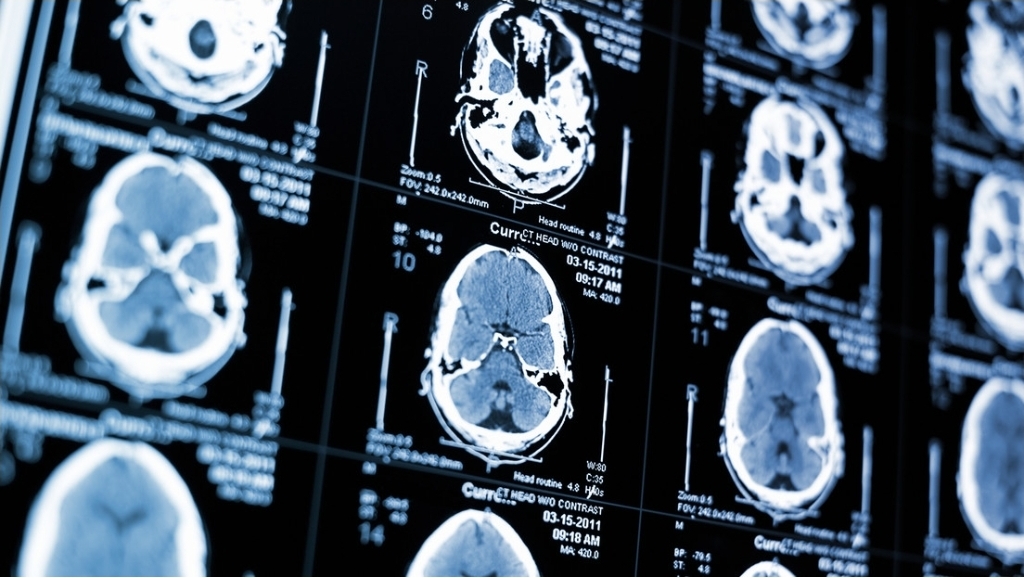

Como parte de un nuevo estudio publicado en la revista Nature Communications, se analizaron más de 2.600 imágenes cerebrales de personas de entre 30 y 97 años. Los científicos observaron que ciertas áreas del cerebro experimentaban distintos cambios con la edad.

Las regiones cerebrales inferiores y frontales tendían a expandirse, mientras que las regiones superiores y posteriores se comprimían. Las variaciones en la geometría del cerebro eran más pronunciadas en adultos mayores con un deterioro en la memoria, el razonamiento y otras funciones cognitivas.

Uno de los hallazgos más relevantes de la investigación apuntó a la corteza entorrinal, una pequeña estructura en el lóbulo temporal medial relacionada con la memoria. Esta zona es una de las primeras en acumular la proteína tau, que está asociada con el alzhéimer, el tipo más común de demencia.

De acuerdo con los investigadores, las deformaciones estructurales del cerebro podrían desplazar físicamente la corteza entorrinal hacia la base del cráneo, lo que podría aumentar la degeneración de esta región. “Esto podría ayudar a explicar por qué la corteza entorrinal es la zona cero de la patología del alzhéimer”, indicó el científico Michael Yassa.

Por otro lado, los resultados, que fueron verificados en dos conjuntos de datos independientes, refuerzan la posibilidad de utilizar la forma del cerebro como un nuevo marcador para detectar el riesgo de sufrir demencia.